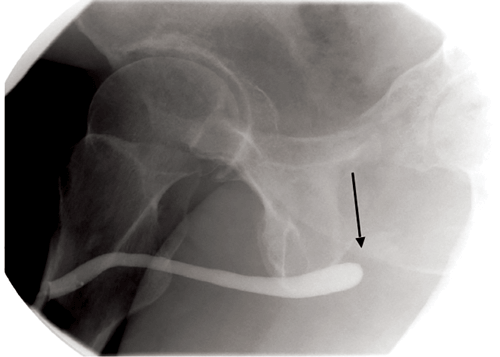

Non-iatrogenic urethral trauma can be divided into anterior and posterior urethral trauma. Non-iatrogenic causes of anterior urethral trauma include blunt trauma, sexual intercourse, penetrating trauma and constriction bands [4]. Posterior urethral trauma is most commonly caused by pelvic fractures, frequently the result of motor vehicle accidents. These injuries are then separated into urethral contusion and partial or complete urethral ruptures. Urethral contusion is when there is urethral stretch but the urethra remains intact [5]. Partial rupture is when there is an incomplete separation of the urethra and there is still part of the urethral wall intact throughout its length. Complete rupture is when the two parts of the urethra are separated, leaving a gap between them which can fill with fibrous tissue. Imaging findings on a urethrogram of a partial rupture would be contrast extravasation, but the presence of contrast within the urethra proximal to the extravasation or additional contrast within the bladder. In a complete rupture you would expect to see contrast extravasation, but no contrast within the bladder [4] (Figure 6 and 7). However, it can be difficult to be sure if the rupture is only partial because contrast does not always enter the bladder on every urethrogram.

Figure 6: Oblique view of an ascending urethrogram demonstrating an abrupt

cut off of contrast at the proximal end of the urethra (arrow).

Figure 7: Oblique view following suprapubic catheter insertion (chevron) demonstrating contrast within the urinary bladder, but no connection between the base of the bladder(white arrow) and the urethra (black arrow), due to urethral transection.